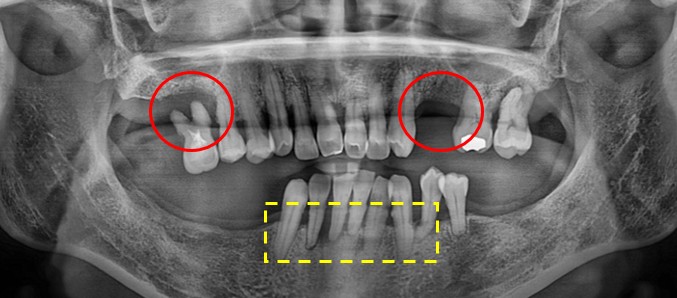

환자분의 초진 구강 사진부터 보도록 할께요.

이미 자연 발치와 치과에서 발치 진단을 받으시고 발치 후 10년 가까이 치아들을

방치 해놓으신 상태라 위의 치아들이 정출되어 내려오기도 하고 관리가 아예 안되신 상태 이셨습니다.

표시된 부분들을 보시면 치아가 거의 공중에 떠있는듯한 모습과 앞니도 이런 교합 관계에 의해

노란칸을 보면 치조골이 소실 된것을 확인 할 수 있습니다.